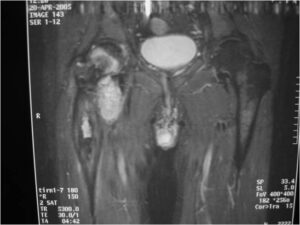

Sites:

- Most common in pelvis, proximal femur, proximal humerus, distal femur, ribs

- Similar sites as conventional chondrosarcoma

Radiographic Presentation

Radiology emulates pathology: Biphasic Tumor

- One region low grade chondrosarcoma

- Second more aggressive area with bone destruction, lysis of calcification, soft tissue mass

- Cortical permeation and a soft tissue mass in 70% of cases

Ill-defined, lytic intraosseous lesion

- Or extraosseous soft tissue mass

- Devoid of calcifications in continuity with lesions having the features of a cartilaginous tumor

Characteristically abrupt transition between chondroid tumor and dedifferentiated, lytic component

Bone may be expanded and adjacent cortex thickened